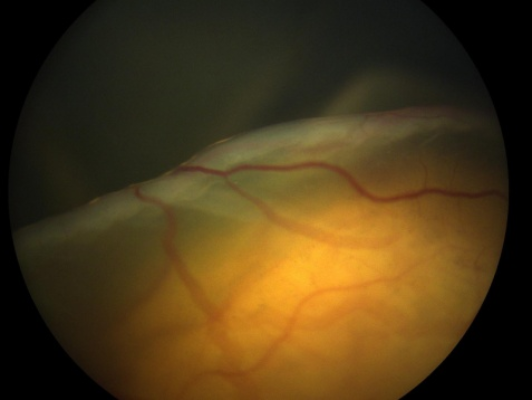

近日,柳女士(化名)的寶寶出生后兩個(gè)月,前往安徽省婦幼保健院進(jìn)行眼底篩查, 結(jié)果左眼被發(fā)現(xiàn)高度可疑視網(wǎng)膜母細(xì)...